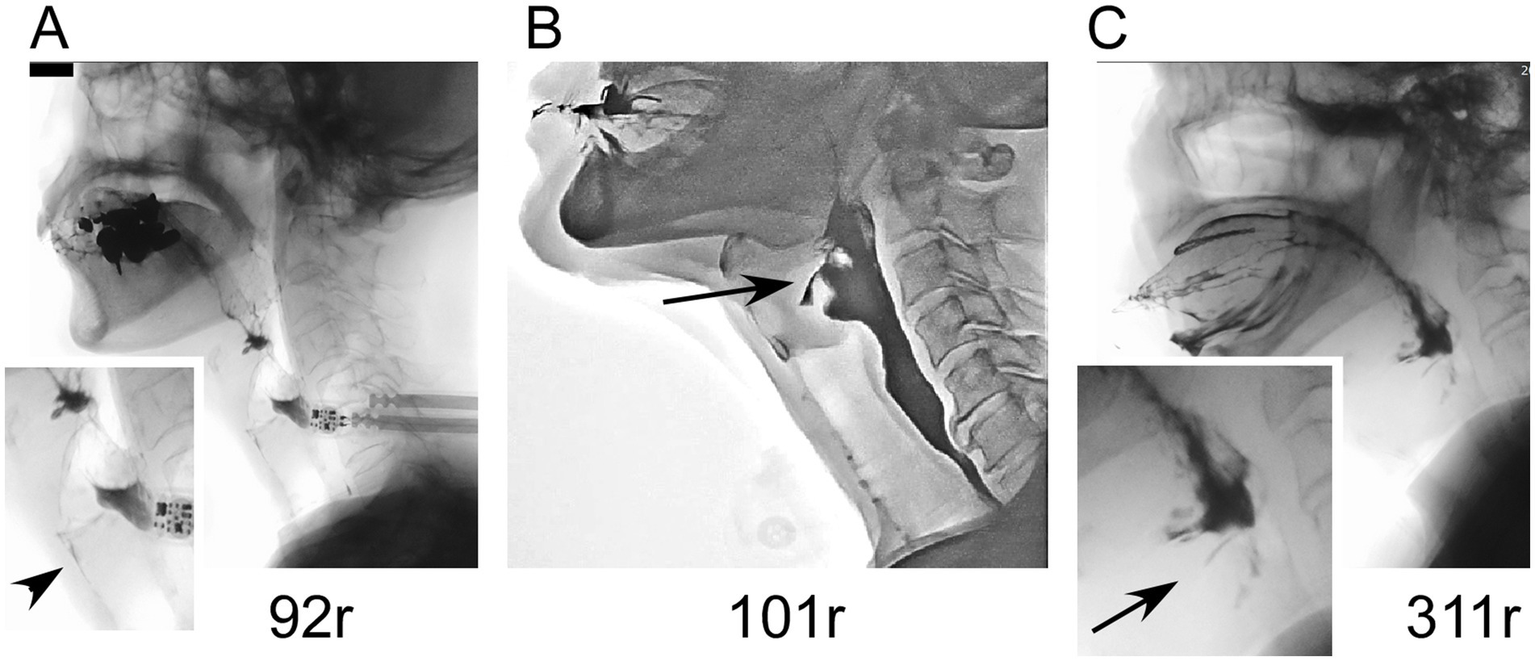

Clinical information about patients with ATXN8OS mutations

The clinical information of the three patients with ATXN8OS mutations in this study, along with previously reported patients, is summarized in Table 1 (14, 15). Our patients responded well to levodopa or the dopamine agonist rotigotine. They seemed to have typical PD symptoms. According to the reported study (32), the phenotypes of our patients were as follows: Patients 1 and 3 were akinetic-rigid type, and Patient 2 was mixed type (Table 1). No patient had cerebellar ataxia. Imaging findings of the three patients with ATXN8OS mutations are shown in Figure 3. Patient 1, with 92 repeats, had no obvious abnormality on MRI. Patient 2 with 101 repeats had an asymptomatic cerebellar infarction with non-specific atrophy in the cerebrum and cerebellum (Figure 3B). Patient 3, with 311 repeats in ATXN8OS, had no obvious abnormality on MRI but showed reduced striatal dopaminergic transporter uptake (Figure 3C). Other patients did not undergo dopaminergic transporter imaging or other functional imaging studies. All patients with ATXN8OS mutations reported swallowing difficulties or discomfort in the throat after eating, which was supported by videofluoroscopic results (Figure 4). Patient 1 exhibited aspiration (Figure 4A), and Patients 2 and 3 exhibited laryngeal penetration (Figs. 4B,C). No correlation was found between the number of repeats and severity or age at onset because the sample size was too small for statistical analysis.

Figure 4

Videofluoroscopic results in patients with ATXN8OS repeat expansions. (A) A patient with 92 repeats underwent aspiration (arrowhead). (B) A patient with 101 repeats had laryngeal penetration. (C) A patient with 311 repeats also had laryngeal penetration.

Interestingly, the three patients with ATXN8OS mutations reported subjective dysphagia, which was confirmed by the objective examination using videofluoroscopic analysis. Patients with PD without mutations also frequently have dysphagia, but only 39% of patients reported subjective dysphagia in our previous cohort (35). The swallowing disturbance found in ATXN8OS mutation-positive patients is reminiscent of our previous finding in ATXN8OS-related ALS, where three of the three mutation-positive patients had bulbar onset or rapid progression of dysphagia (9). We speculate that neurons associated with swallowing may be susceptible to the expanded repeats in ATXN8OS.